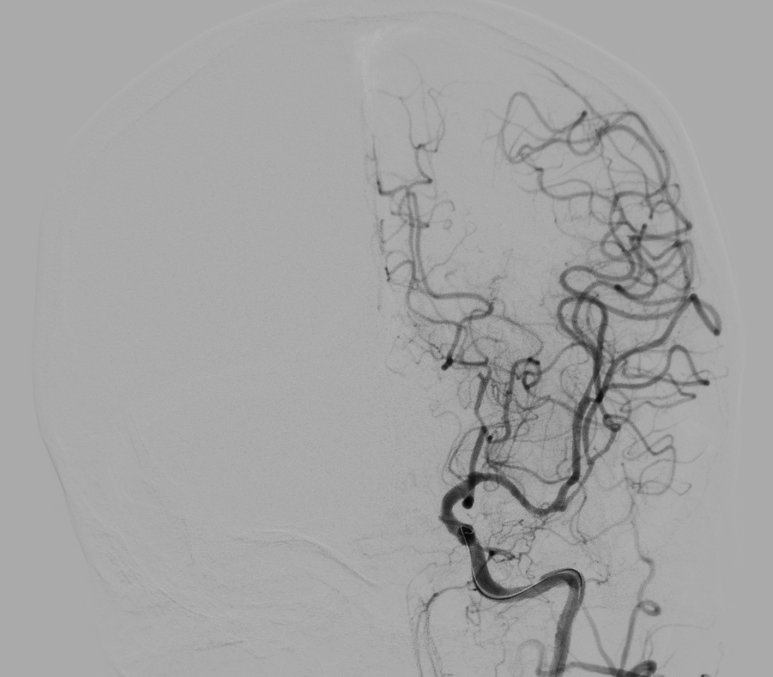

神经介入诊疗中心主任、副主任医师刘俊中接诊后,根据各项检查检验结果迅速判断张女士属于颅内大血管病变。

左侧大脑中动脉和颈内动脉均已闭塞,相当于左侧大脑半球几乎断了供血,手术指征明确。

5 分钟后,张女士被推进介入手术室,急诊脑血管造影进一步确认了血管闭塞情况。

10 分钟后,手术顺利完成,堵塞血管成功开通,濒临坏死的脑细胞被及时 “救回”,张女士的病情得到了有效控制。